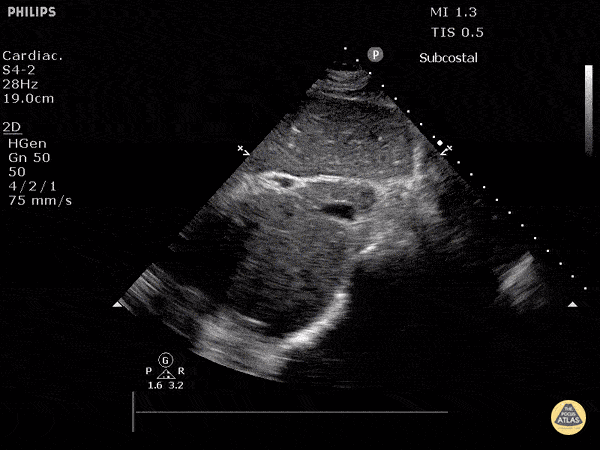

IVC & Abnormal Venous Waveforms - Inferior Vena Cava in Hypovolemia